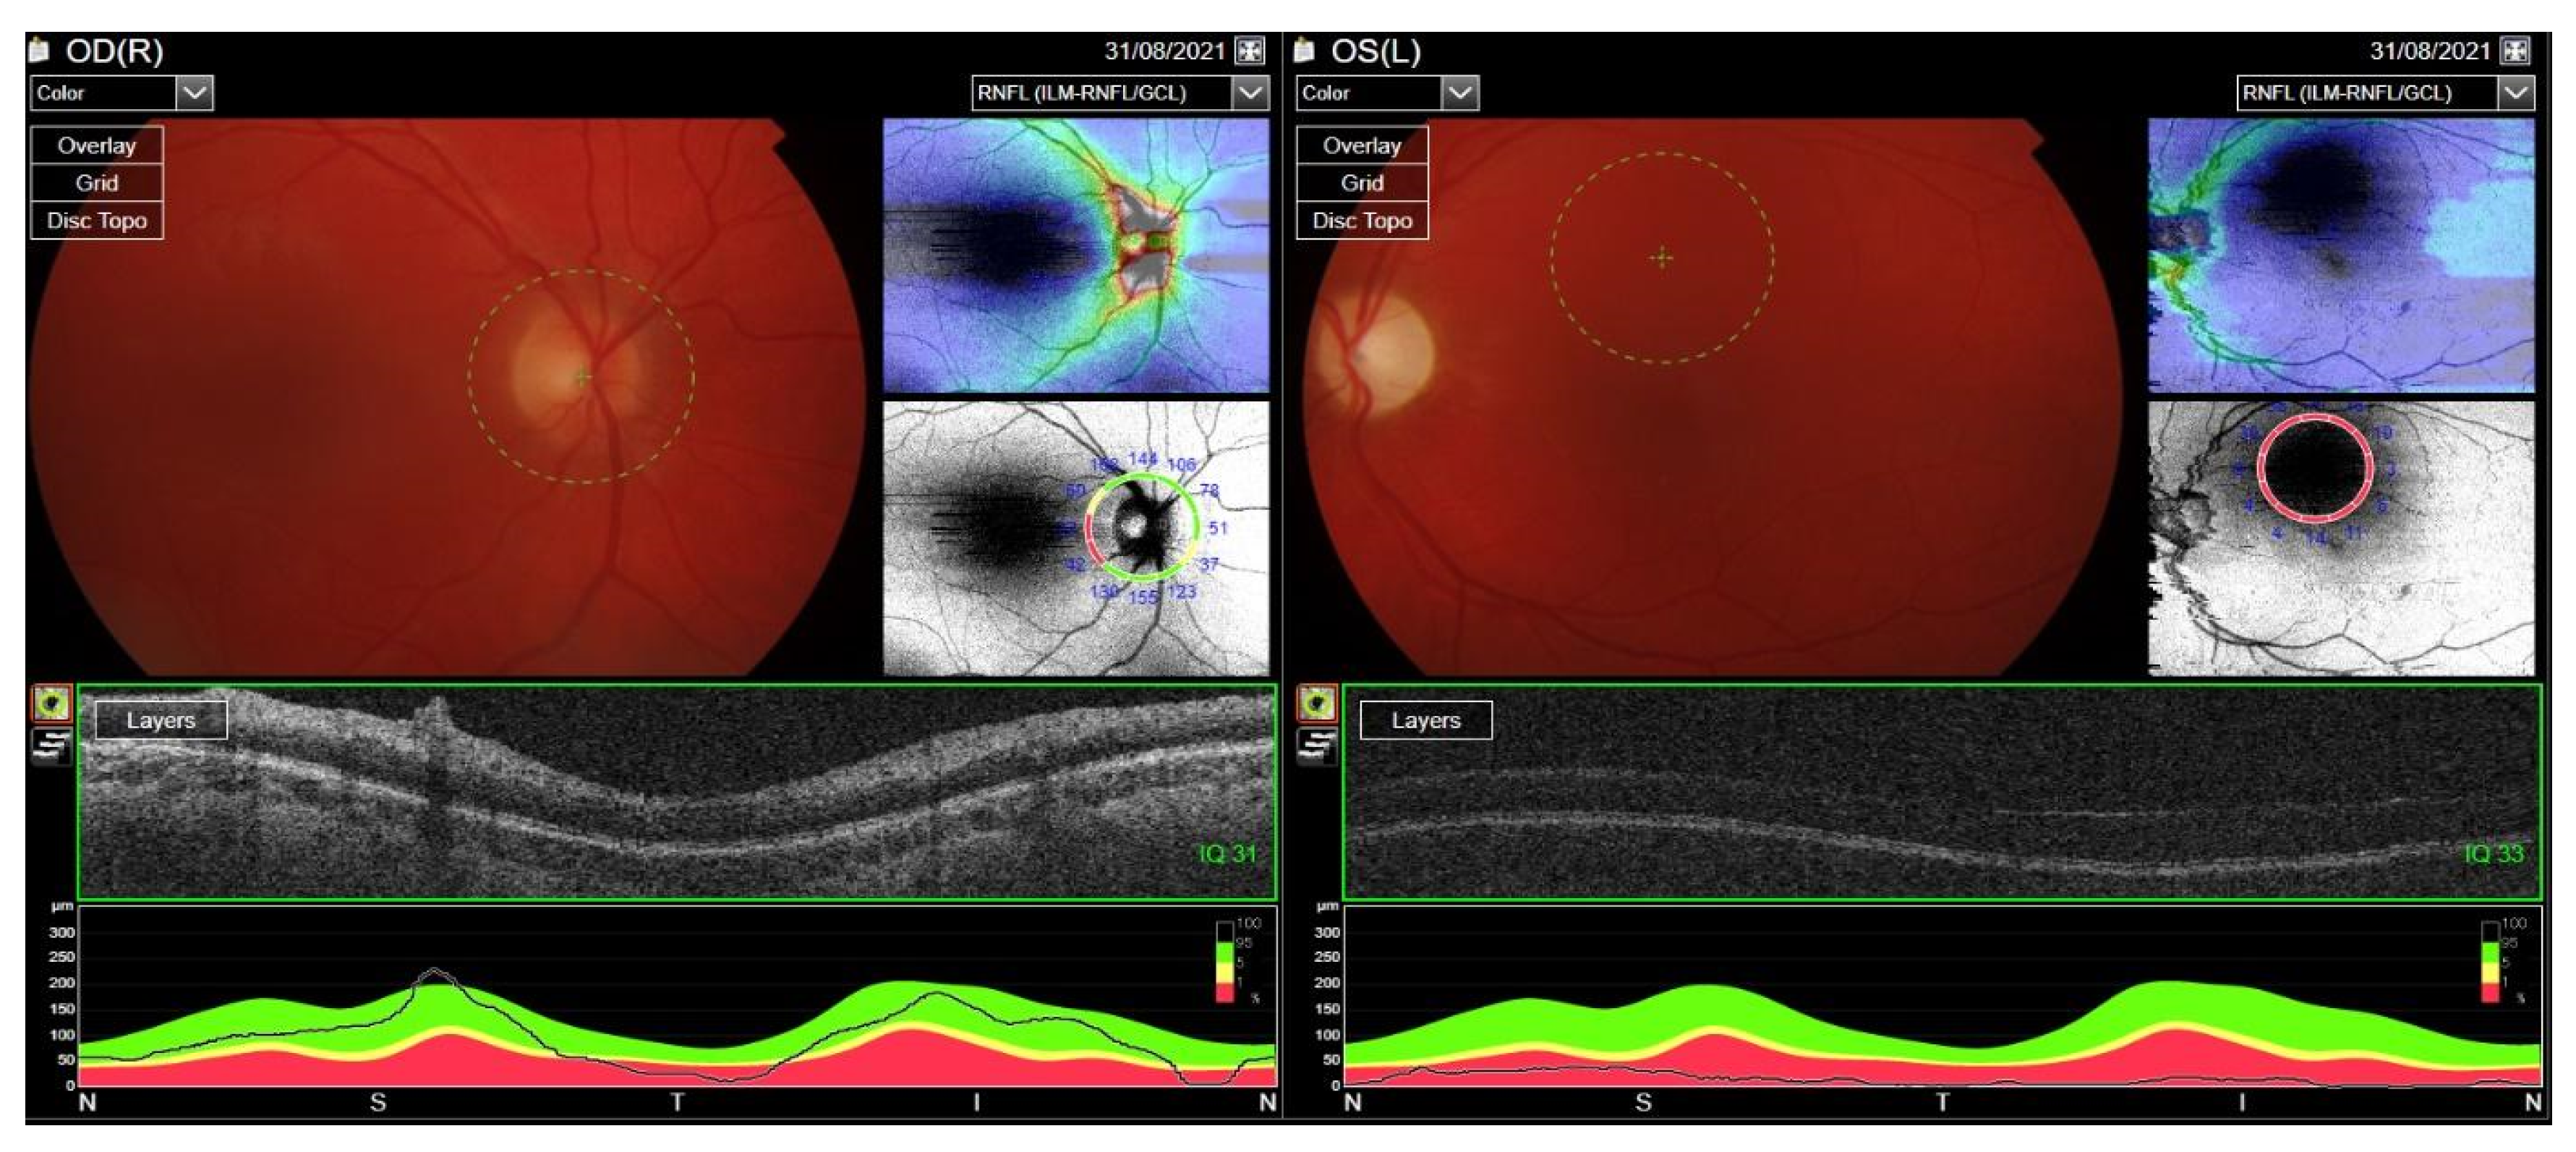

Treatment with RTX was reintroduced. Cyclosporine dose was increased to 200 mg/day and methotrexate up to 30 mg/week. After the RTX therapy course, the ocular assessment revealed a quiet eye with left compressive optic neuropathy (a pale disc with RNFL atrophy) and bilateral posterior subcapsular cataracts (Figure 16). The final visual acuity was logMar 0.0 in the RE and light perception in the LE.

Figure 16. Fundus OCT and RNFL image. Optic disc pallor following compressive neuropathy in the LE. Difficulty with fixation due to light perception in the LE.